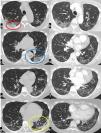

Case 1: 78 years-old male. In the supine position, focal pure ground glass opacities were present in both upper lobes, and some peripheral part-solid ground glass areas with a coexisting crazy paving attenuation in both costophrenic angles. Furthermore, the peripheral branches of the pulmonary veins of the lower lobes appeared enlarged. In the prone position a significant decrease in diameter of veins and a kind of parenchymal ground glass attenuation in both lower lobes. Moreover, a rapid reduction of the density was observed in the “former crazy paving component” that changed into pure ground glass attenuation (Fig.1).

CT scan in supine (a,c) and prone (b,d) position. Some rounded areas of pure ground glass attenuation are present in the right upper lobe (a, upward yellow arrow), middle lobe and lingula. The GG attenuation in right upper lobe, in prone becomes crazy paving and is associated with occurring of an inside vessel enlargement (b, downward yellow arrow).

In the right lower lobe a part-solid ground glass attenuation with a coexisting minimal crazy paving pattern, is present beneath the pleura (c; red ellipse) in the apical and postero- basal segments.

Some vessel enlargement is present in both lower lobes. In the right lower lobe, the enlargement is both outside and inside the GG attenuation and involves branches of the pulmonary veins (caliber of 4.6 mm). Finally, in the left lower lobe, a nodular consolidation is present, adjacent to the pleura (pink arrow), with a drastic reduction in density with the prone positioning.